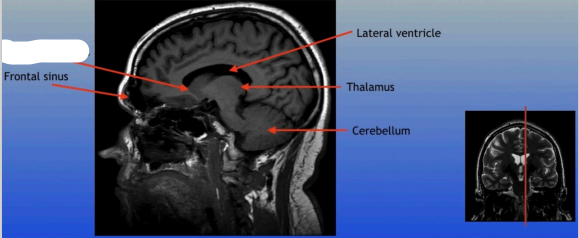

Frontal Sinus

A paired cavity located within the frontal bone, above the eyes, that plays a role in sinus drainage and resonance of the voice.

Frontal Sinus

A paired cavity located within the frontal bone, above the eyes, that plays a role in sinus drainage and resonance of the voice.

Lateral Ventricle

A fluid-filled cavity located within each hemisphere of the brain, part of the ventricular system, that helps cushion the brain and circulate cerebrospinal fluid.

Thalamus

A large mass of gray matter located in the diencephalon, acting as a relay station for sensory information and playing a key role in regulating consciousness and sleep.

Cerebellum

A large structure located at the back of the brain responsible for coordination, balance, and fine motor control.